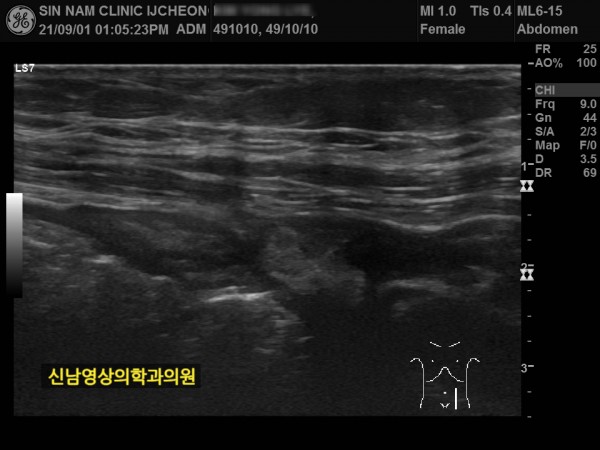

1년 뒤 수술 부위에 탈장이 발생하셔서 탈장 수술을 받으셨던 분입니다.

상복부 초음파 검사는 간, 담낭, 담관, 췌장, 신장, 비장 등 상복부 주요 장기를 초음파로 실시간 영상화해 진단하는 검사입니다.

구조와 이상有無를 확인합니다.

지방간, 간염, 간경변, 간암, 담석증, 담낭염, 췌장염, 신장 결석, 종양 등 다양한 질환을 진단할 수 있습니다.